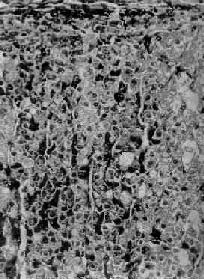

图15-13 肾上腺皮质弥漫增生(大体) 肾上腺肥大,皮质弥漫性增厚,切面呈脑回状

图15-14 肾上腺皮质弥漫增生 图15-13之镜下观,肾上腺皮质束状带弥漫性增厚 2.异位分泌ACTH或CRF肿瘤肾上腺变化与上述同。 3.肾上腺皮质结节性增生(adrenocortical nodular hyperplasia)其原因不明,有的呈家族性。双侧肾上腺明显肥大,重量可超过50g,在弥漫增生的基础上又有许多增生的结节,大小不等,直径从数毫米至2.5cm。镜下,弥漫增生者主为网状带及束状带细胞,而结节内多为束状带细胞,常见多量脂褐素,致结节呈棕褐色。患者血清ACTH水平下降。 4.功能性肾上腺肿瘤 除肿瘤变化外,血清中ACTH减少,致使肾上腺非肿瘤部分萎缩。 5.长期使用糖皮质激素类药物 例如地塞米松(dexamethasone),由于反馈抑制垂体前叶释放ACTH,故血清中ACTH等减少,双侧肾上腺皮质萎缩。 (二)醛固酮增多症 原发性醛固酮增多症(primary aldosteronism)是肾上腺皮质增生的细胞分泌过多的醛固酮所致,引起高血钠症、低血钾症及高血压。本症血清中肾素降低,这是由于钠潴留使血容量增多,抑制了肾素的释放。本病80%是由于功能性肾上腺肿瘤引起,其余为原因不明的两侧肾上腺皮质增生等,这种增生常呈弥漫性,有时也呈结节状,镜下主要为球状带细胞增生,有时也混杂些束状带细胞。 继发性醛固酮增多症是由于各种疾病造成肾素分泌增多所致,肾素可使血浆中的血管紧张素原转变为血管肾张素,后者刺激球状带细胞使醛固酮的分泌增多。